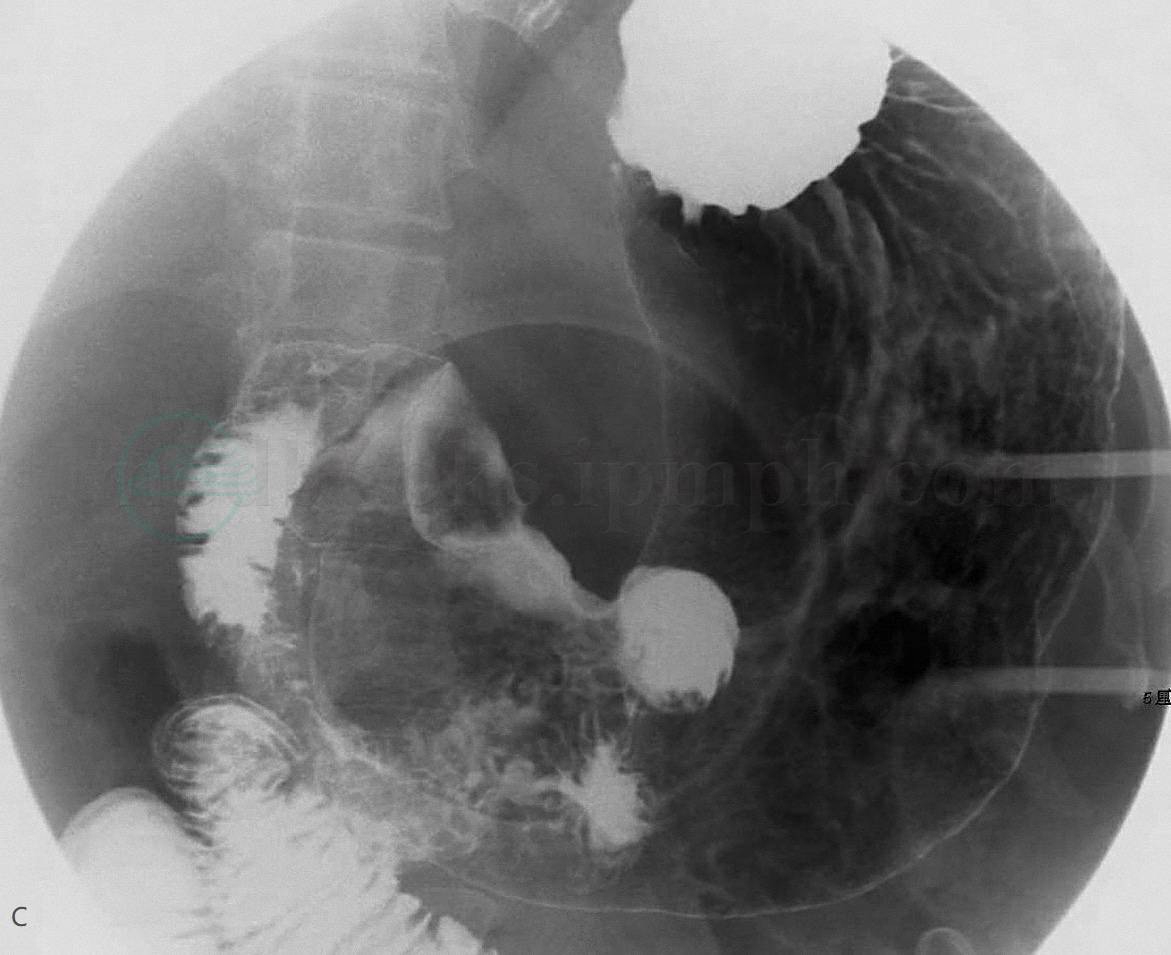

图1 胃窦部黏膜下层纤维脂肪瘤

A、B. CT增强扫描横断面示胃窦近后壁处凸向胃腔内生长的结节影(白箭),大小约3.0cm×2.0cm,边界清楚,病变密度略不均匀,以脂肪密度为主;C、D. 胃气钡双对比造影:胃窦小弯侧见一充盈缺损(黑箭),凸向胃腔内,大小约1.9cm×3.3cm,局部黏膜规则,未见龛影,胃壁柔软